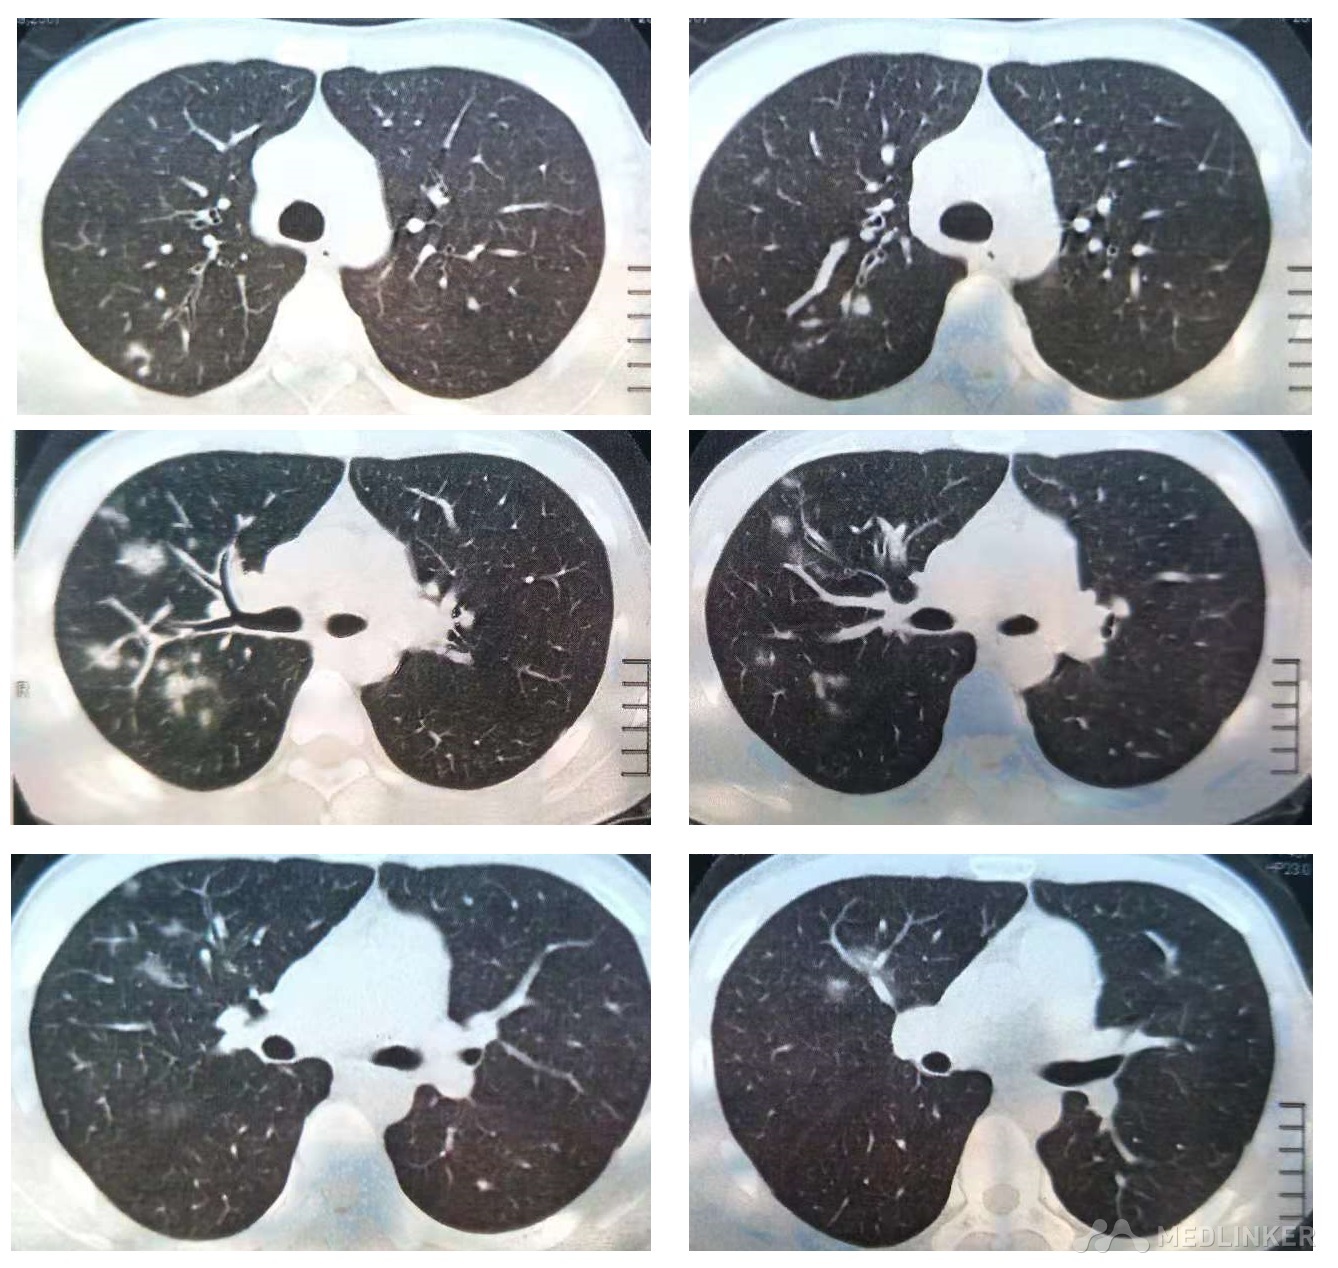

支原体肺炎CT

支原体肺炎影像分析

成人支原体肺炎的ct表现

肺炎支原体ct片分享

9岁男童,咳嗽近一周入院,查胸片有炎症,查ct如下,肺炎支原体抗体阳性

一眼就认出你是支原体肺炎而不是肺结核

诊断篇:肺炎支原体肺炎的影像学诊断

肺炎支原体肺炎时ct怎么看